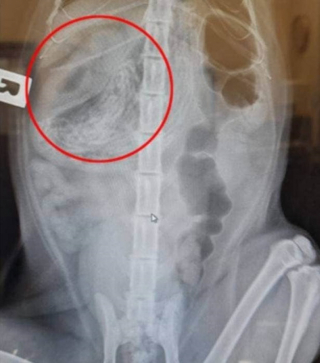

Étant elle-même infirmière vétérinaire, elle a conduit son chat dans le cabinet où elle travaillait. Grâce à une radiographie, le vétérinaire a détecté ce qui semblait être une tumeur dans l’estomac de Nermal.

Dès le lendemain, le félin a été opéré. Les vétérinaires ont été à la fois stupéfaits et soulagés lorsqu’ils ont découvert qu’il ne s’agissait pas d’une tumeur, mais d’un amas de 37 élastiques à cheveux. A priori, le chat les avait accumulés pendant près de 4 ans. Par chance, ceux-ci n’étaient pas allés plus loin que l’estomac et n’étaient pas entrés dans ses intestins. Le chat n’avait jamais montré de signes alarmants. Il mangeait normalement et ne vomissait pas, ce qui est assez surprenant.